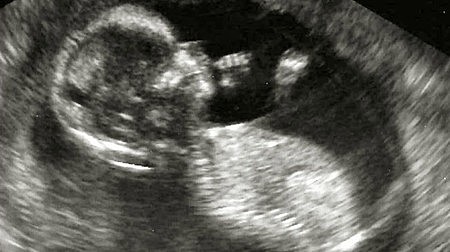

-Las porciones cartilaginosas que hasta el momento han formado el esqueleto del feto, se transforman en tejido óseo.

-Mide entre 12,5 y 14 centímetros y pesa unos 150 gramos.

-Ya se visualiza el corazón fetal funcionando mediante ecografía.